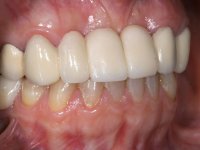

The patient did not like her smile, said that she had "very artificial looking teeth".

In view of the clinical situation, oral rehabilitation was proposed to improve the aesthetic appearance, but also to solve the lack of posterior teeth, seeking a functional and aesthetic rehabilitation. The plan included replacing the metal-ceramic bridge by a bridge with Zr infrastructure coated with coronary and gingival ceramics. The edentulous area of the first quadrant would be rehabilitated with 2 implants and a bridge of two elements. It was intended with this treatment plan, to recover the vertical dimension of the occlusion and to reshape the dental anatomy, thus creating a more natural aesthetic appearance.

Alginate impressions were made at both arches arcades, accompanied by intermaxillary registration relations and collecting information with facial bow facial bow. In the laboratory, a provisional bridge with 13 elements in autopolymerizable acrylic was built, in which a metallic reinforcement was included. Teeth 1.7 / 1.4 / 1.3 / 2.2 / 2.3 / 2.4 and 2.6 were used as pillars. The metal-ceramic bridge was removed after performing longitudinal cuts with diamond burs. The dental abutments were reprepared and the temporary bridge was relined in the mouth with self-curing acrylic. After confection of the provisional bridge, a gingival epithesis was made using composite resin with gingival tonality in order to function as a mock-up, which allowed the patient to preview the possibility of using gingiva shade ceramics in the final work. This option was approved by the patient. Subsequently, the placement of two implants in the first quadrant was planned and executed. The provisional monoblock was removed for placement of the implants, and after surgery was again cemented provisionally. After the osseointegration period, the impressions were made to the maxilla. In the anterior zone, impregnated gingival retraction cords were used, and in the posterior areas, kaolin paste was used. Implant printing utilized the open tray technique. The printing material used was soft and regular putty addition silicone, both fast-setting. In the laboratory, the model of provisional restorations and the gingiva epithesis mock-up served as orientation for waxing the infrastructure. The plaster work model and the waxing of the infrastructure were placed in a laboratory scanner and yielded a digital work model, in which the scanning of the waxed infrastructure was superimposed. This overlay facilitated the CAD design of the Zr infrastructure. Subsequently, the CAD drawing for a CAM milling process provided the Zr pieces. The infrastructure was pigmented with a pinkish coloration, which favors the subsequent placement of gum shade ceramic. During the modeling of the infrastructure, the need to increase the occlusal wear on tooth 1.4 was detected. This was done in the real working model cast and an acrylic wear control guide was created, which accompanied the proof of the infrastructures. Corrective wear and Zr parts test were performed in mouth. During the test, the color choice of the gum shade ceramic was reassessed. The treatment was finished in the laboratory, and after approval by the patient, was definitively placed in the mouth.